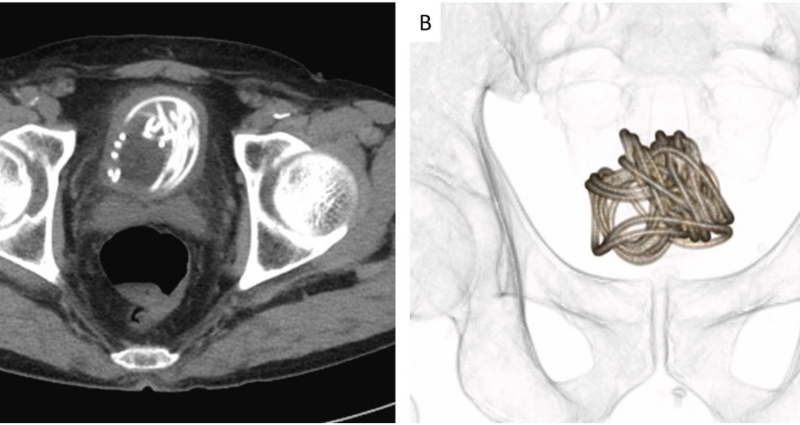

ជប៉ុន៖ បុរសអាយុ ៧៩ម្នាក់បានធ្វើឲ្យក្រុមវេជ្ជបណ្ឌិតមានការភ្ញាក់ផ្អើលយ៉ាងខ្លាំង ក្រោយគេបានគេឃើញមានខ្សែដ៏វែងមួយនៅក្នុងប្លោកនោមរបស់គាត់។ យោងតាមការចុះផ្សាយរបស់បណ្តាញសារព័ត៌មាន Next Shark កាលពីថ្ងៃអង្គារ ទី១៥ ខែវិច្ឆិកានេះបានឲ្យដឹងថា ហេតុការណ៍នេះបានកើតឡើងនៅក្នុងមន្ទីររបស់សាកលវិទ្យាល័យវេជ្ជសាស្រ្ត Dokkyo ស្ថិតនៅក្នុងទីក្រុង Mibu នៃប្រទេសជប៉ុន។